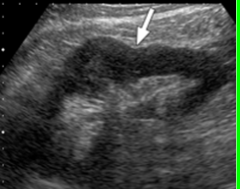

Hydronephrosis

Obstructive disease of the urinary system – dilatation of calyces and renal pelvis with urine. Long term can cause atrophy and loss of renal function.

Clinical indications for hydronephrosis

Most common cause is calculus/stone. Signs/Symptoms include flank pain and blood or pus in urine. May have abnormal labs if damage is present.

hydronephrosis image